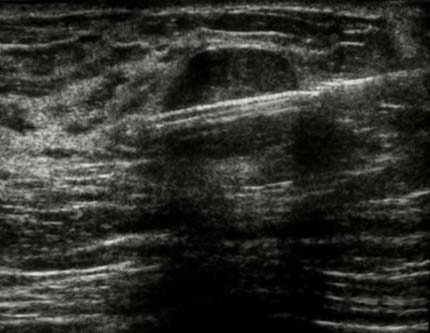

Un médecin peut décider de recourir à une biopsie percutanée suite à la détection d’une excroissance ou d’un changement suspect des tissus lors d’un examen physique, d’une échographie ou d’une mammographie. L’opération consiste à prélever des tissus à l’aide d’une aiguille en vue de les analyser pour déterminer s’il s’agit ou non de lésions cancéreuses.

Lorsque l’anomalie est bien visible à l’échographie, le radiologue choisit souvent cette technique pour diriger l’aiguille. On dit alors que le prélèvement est échoguidé.